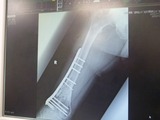

ºòÆü¤ÎROC¤Ë¤Æ2¥³¡¼¥Ê¡¼¤ò¥³¡¼¥¹¥¢¥¦¥È¤·¤Æ·ãÆÍ¤·¤Þ¤·¤¿¡£

¤Û¤Ü¥Î¡¼¥Ö¥ì¡¼¥¤Ç

ÀµÌ̤«¤é´Ë¾×ºà¤Ë·ãÆÍ¤·¤Þ¤·¤¿¡£

¤½¤Î¤Þ¤ÞÎ뼯¥µ¡¼¥¥Ã¥È¤Î¥á¥Ç¥£¥«¥ë¤Ë¤Æ

¿Ç»¡¤ò¼õ¤±¤Æ¡¢ËÜÆü¼ç¼£°å¤Î¿Ç»¡¤ò¼õ¤±¤Þ¤·¤¿¡£

¹¬¤¤¤Ê»ö¤Ë¹ü¤Ë°Û¾ï¤Ï̵¤¯°ì°Â¿´¤Ç¤¹¤¬

¶¯Îõ¤ÊÁ´¿ÈÂÇËФÈ

±¦¤Ò¤¸¤¸¤óÂÓ»½ý¤Ç

Á´¼£2½µ´Ö¤ÎÆþ±¡²ÃÎŤò¿ÇÃǤµ¤ì¤Þ¤·¤¿¤¬

Æþ±¡·ù¤¤¤ÎËͤλö¤òʬ¤«¤Ã¤Æ¤¤¤ë

¼ç¼£°å¤ÎȽÃǤˤơ¢Ìµ»ö¤Ë³«Êü¤µ¤ì¤Þ¤·¤¿¤¬

¤¢¤Þ¤ê¤Î·ãÄˤ椨¡¢Ä̾ï¶È̳¤¬½ÐÍè¤ë¾õÂ֤ǤϤʤ¤¤Î¤Ç

»Ã¤¯¤Î´Ö¡¢»ö̳½èÍý¤Ê¤É¤·¤«½ÐÍè¤Þ¤»¤ó¡£